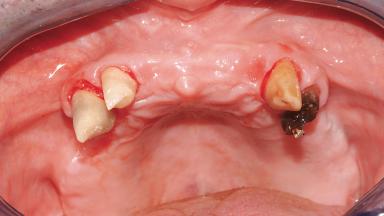

Immediate Loading of Six Implants in the Maxilla and Final Restoration with a Full-Arch Gold/Ceramic FDP Involving the Concept of Tilted Implants

A 61-year-old male patient with a failing fixed maxillary rehabilitation and a fixed mandibular rehabilitation requested a new fixed maxillary rehabilitation. The patient was wearing a temporary metal-reinforced maxillary bridge inserted two years before the consultation. He reported that his previous dentist did not want to insert a definitive framework because he considered the residual teeth to have a negative prognosis. The patient reported a history of recurrent caries and endodontic complications as the main reason for the previous extractions. The anamnesis was negative for periodontal disease and bruxism. The patient’s chief compliant was the mobility of his maxillary prosthesis, which needed to be re-cemented frequently, and discomfort during chewing.Moreover, the patient was not satisfied with the esthetic appearance of his maxillary teeth, which he found too long. The patient asked for a stable and comfortable fixed maxillary rehabilitation and firmly rejected any removable solution.

Bone Volume Deficient horizontally, allowing simultaneous augumentation